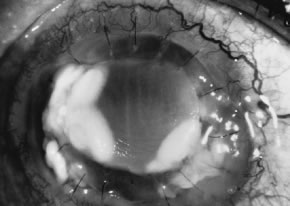

In the early stages of infection, filamentous fungi produce signs that are readily distinguishable from yeast or bacterial keratitis. The most distinctive sign is the presence of delicate, fine, feathery, opalescent, gray-white or yellow-white material in the anterior stroma, surrounded by scant cellular infiltrate or edema (Fig. 1). The epithelium may be intact. The overlying epithelium may be granular and the surface elevated and irregular in contour. Linear infiltrates typically extend into the adjacent stroma. Multiple discrete opacities may develop outside the perimeter of the principal focus of inflammation, either separated by clear stroma or linked by fine linear collections of inflammatory cells and material (Figs. 2 and 3). In the absence of inflammation in the adjacent stroma, branching hyphal fragments may be visualized by biomicroscopy (Figs. 4 and 5). Confocal microscopy may also detect hyphal elements within the stroma.28,29 Peripheral infection resembles noninfectious marginal infiltrative and ulcerative keratitis (Fig. 6). Multifocal keratitis may develop after contact lens wear or injury by multiple projectiles (Fig. 7). In the early stages, iritis is present and the intraocular pressure remains normal. Inappropriate, empirical therapy of fungal keratitis with topical fluoroquinolone or aminoglycoside antibiotics may suppress or eliminate the superficial elements but allow extension of the organisms into the stroma because these agents may possess selective antifungal activity.4,30,31

There is no distinguishing clinical sign by which to recognize the genus or species of the infectious filamentous fungus. F. solani is the most virulent organism and typically produces rapidly progressive infection characterized by epithelial and stromal ulceration, dense stromal necrosis, abundant cellular infiltrate, and edema in the adjacent stroma and hypopyon (Figs. 8 and 9). Delicate feathery components are transient. Individual hyphal fragments are rarely visualized. Infection by certain species of Aspergillus and Scedosporium (Figs. 10 and 11) resembles F. solani keratitis and progresses rapidly. Infection by less virulent organisms, such as Curvularia and Alternaria species, produces small, focal (less than 3-mm diameter) areas of nonnecrotizing stromal inflammation with delicate feathery borders (see Fig. 1 and Fig. 12). Macroscopic pigmentation may develop in keratitis caused by Alternaria, Curvularia, and other dematiaceous fungi (Fig. 13).4,11,14 The central component may progress to dense, opaque, gray-white suppuration in the deep stroma without enlargement in total area and may be accompanied by mild inflammation in the adjacent stroma. Iritis is minimal to moderate. Infection caused by other, relatively less virulent organisms resembles herpes simplex or noninfectious keratitis (Fig. 14).